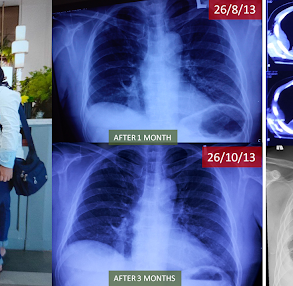

At some point, I understood that I needed more support. I contacted the ECCT team, and they explained to me how ECCT works. During the initial consultation, the team carefully reviewed my medical history, imaging, biopsy results, and symptoms. They encourage me to get proper biopsy and told me that it is likely recurrent of metastatic TNBC. The scan later on does confirm it’s TNBC involving my liver, bone, lung, and lymph nodes. The biopsy as well confirmed a highly aggressive recurrence. The tumour was again triple-negative, now with a Ki-67 of 90%, extensive necrosis, numerous atypical mitoses, and no PD-L1 expression, these features associated with fast growth and limited immunotherapy options.

By December 2025, PET-CT imaging showed a clear and significant treatment response for my resolution of TNBC Ki-67 of 90%:

– Liver metastases had markedly reduced in size and metabolic activity

– Bone lesions were less active

– Lung nodules showed improvement

– The ulcerated breast tumour had become significantly smaller